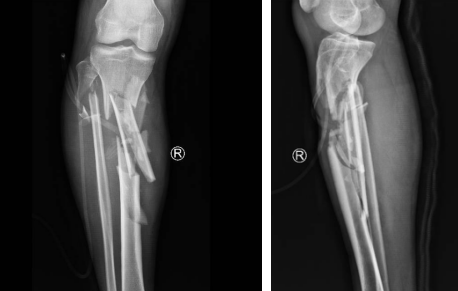

小张一场意外车祸导致小腿胫骨粉碎性骨折,在仁慈医院进行了骨延长手术,得知曹广超主任来看望他后,早早来到门口等待。

“当时医院都要截肢了,多亏转到了仁慈,保住了这条腿,现在好的很,开车带孩子去云南玩,这要截肢了哪敢想。”

胫骨粉碎性骨折,伴有腓总神经损伤

骨延长术后